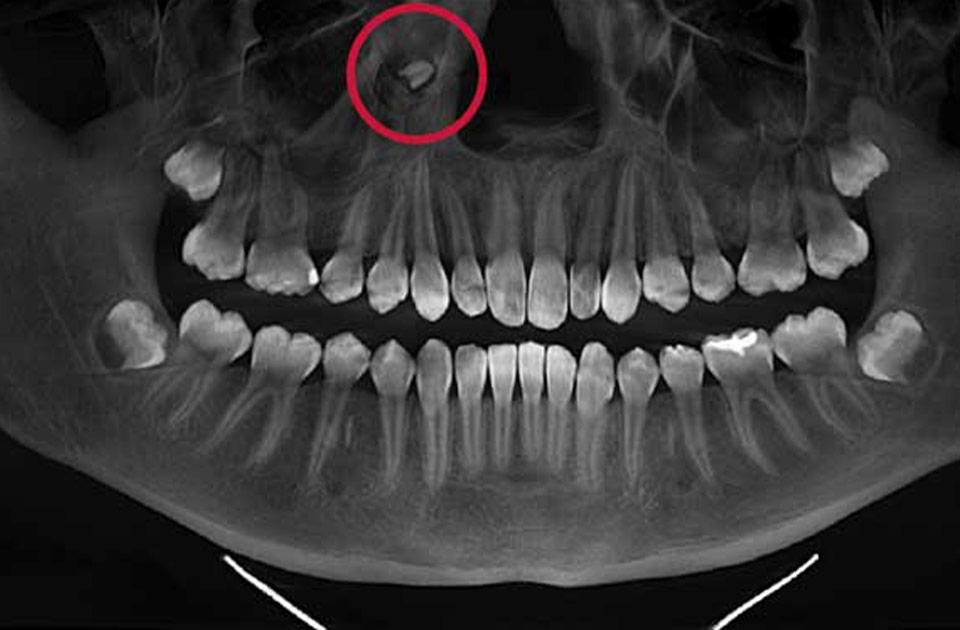

تشخیص هایپردونتیا معمولاً از طریق معاینه دندانپزشکی و استفاده از عکسبرداری رادیولوژی انجام میشود. با بررسی تصاویر، دندانپزشک میتواند تعداد و موقعیت دندانهای اضافی را مشخص کند و برنامه درمانی مناسبی را برای بیمار تدوین کند.

2. عکس برداری رادیولوژی: با استفاده از عکسبرداری، دندانپزشک میتواند دندانهای اضافی را که ممکن است در عمق فک قرار داشته باشند، شناسایی کند.